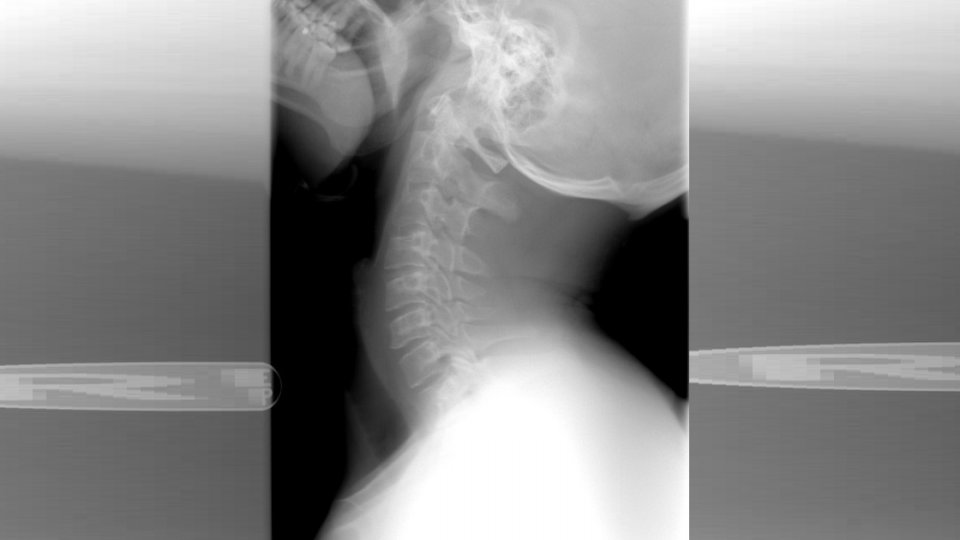

3 simptome unice pentru osteoartrita cervicală

Osteoartrita este o patologie care afectează coloana cervicală în aproximativ 75% din cazuri. Într-adevăr, osteoartrita cervicală este frecventă și este responsabilă de un set de simptome precum, pe lângă dureri de gât, migrene, rigiditate cervicală etc.